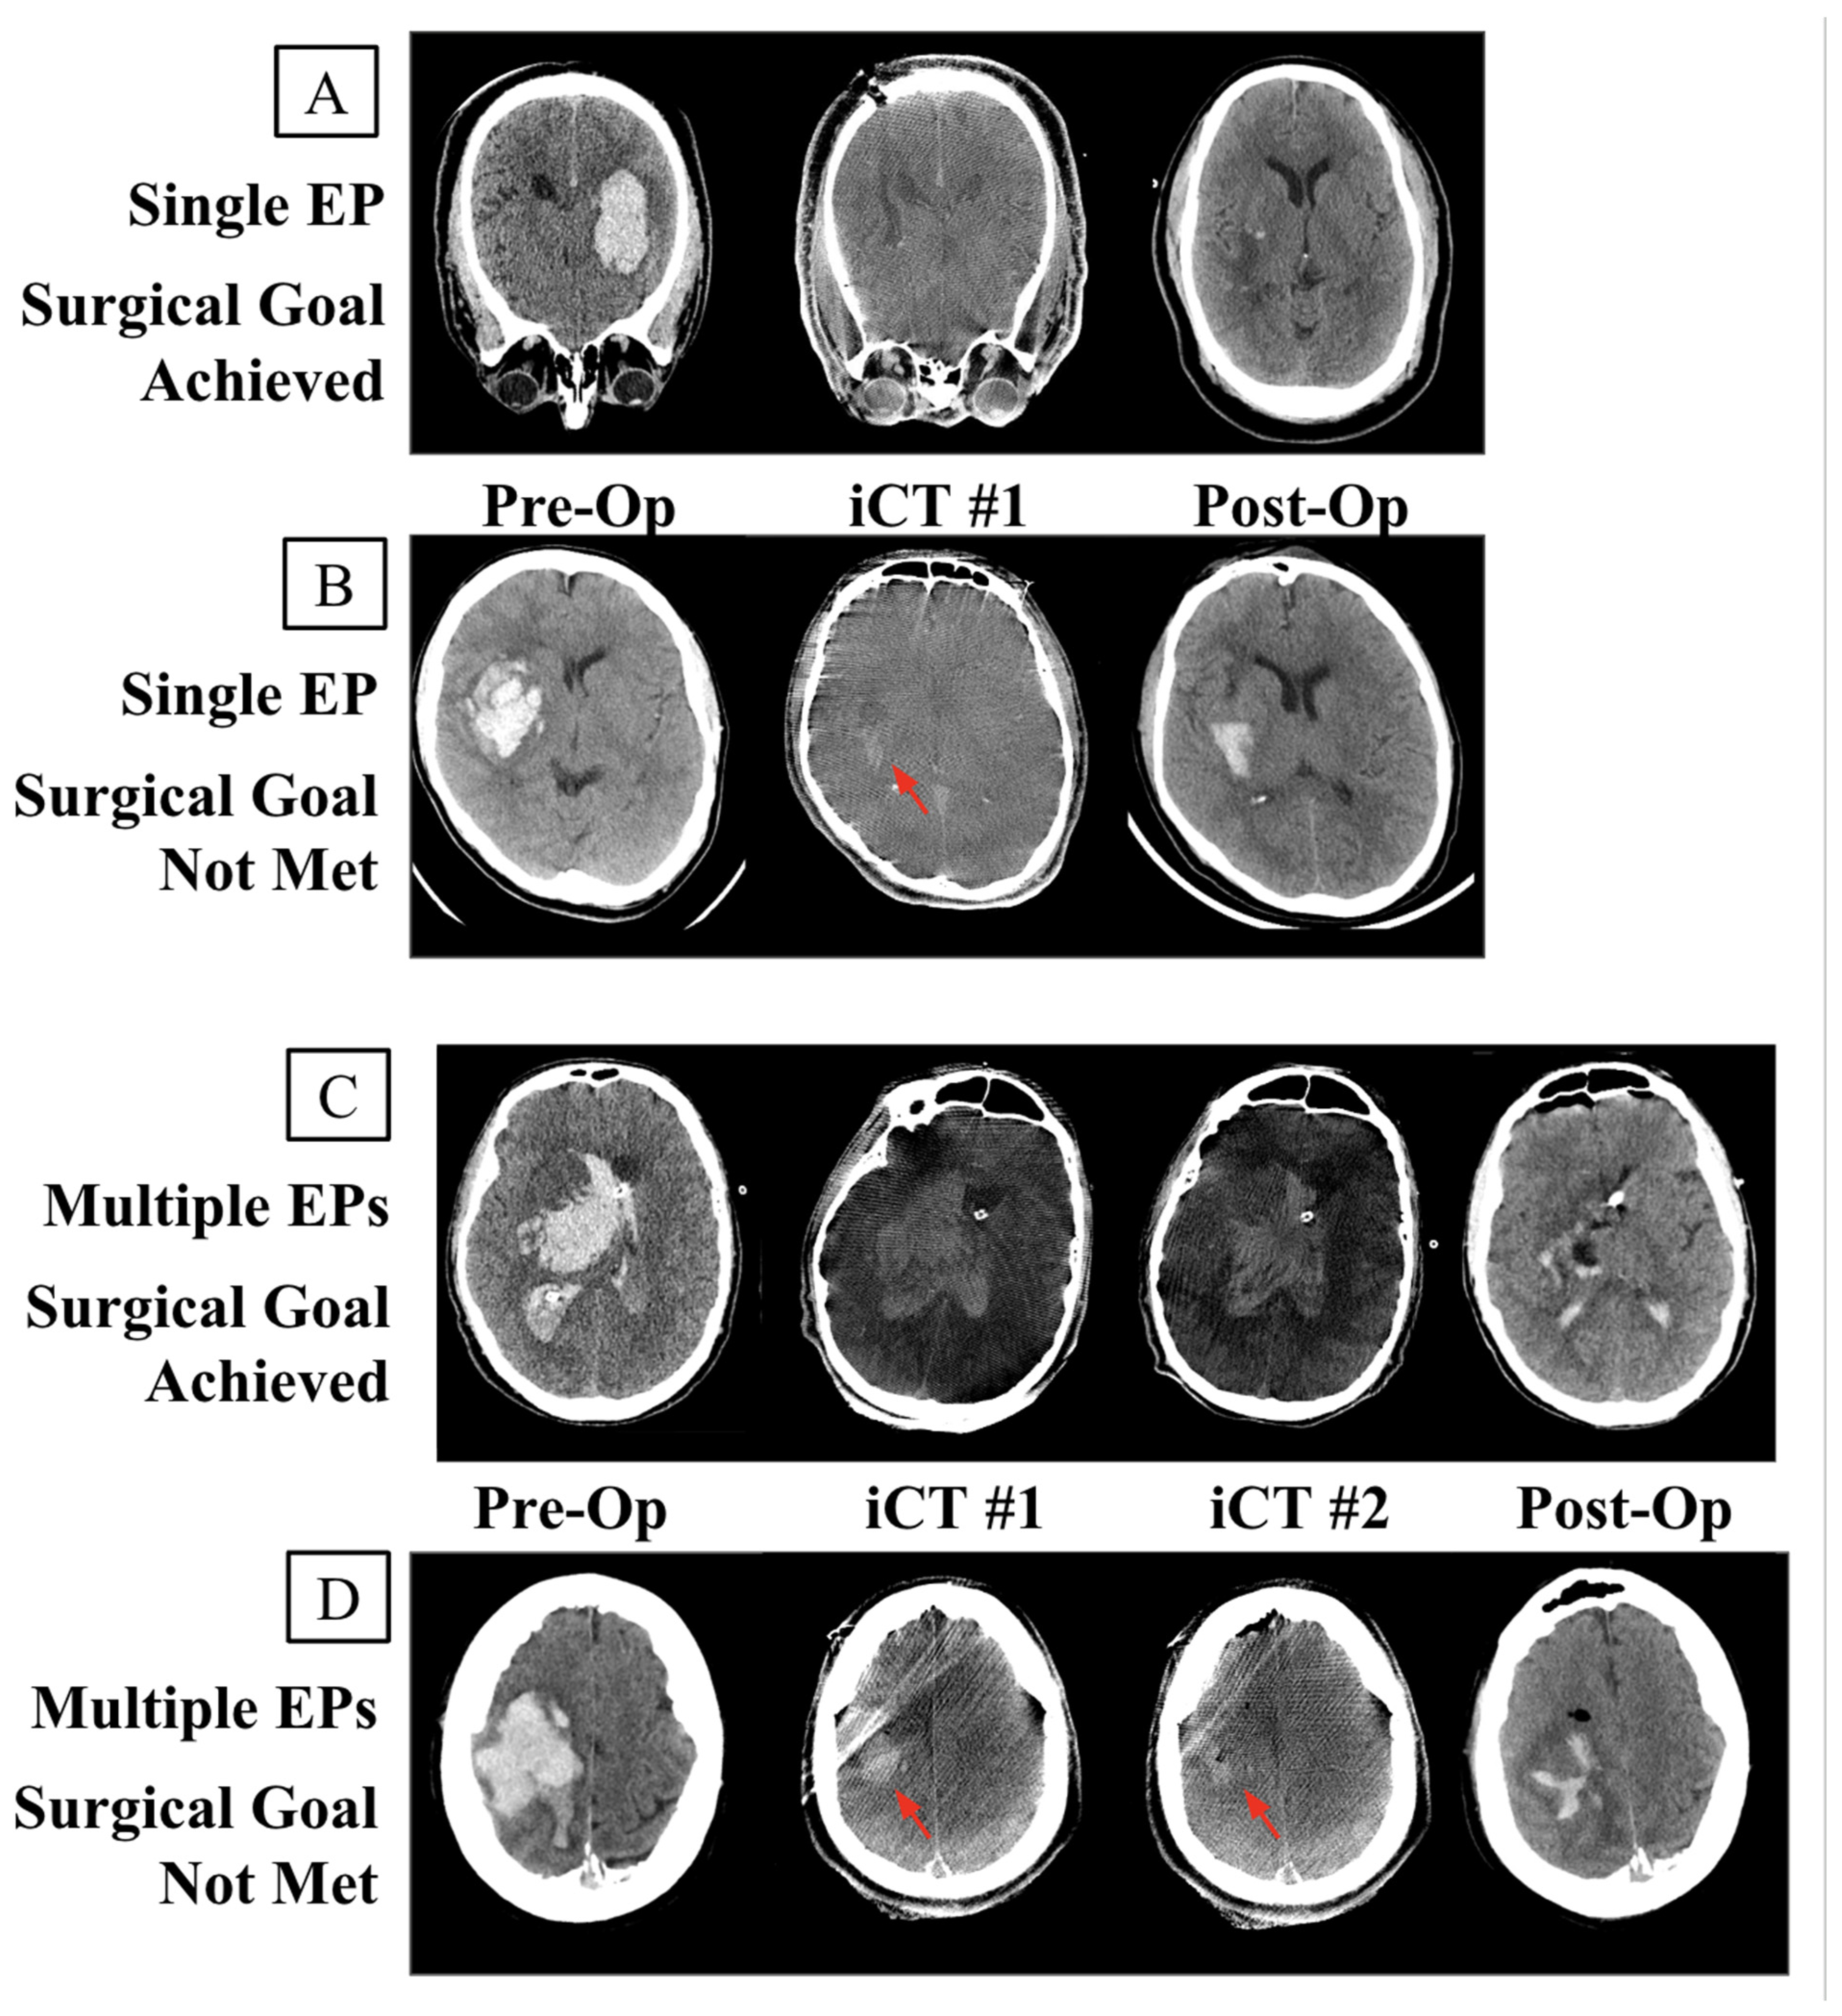

| EP | evacuation period |